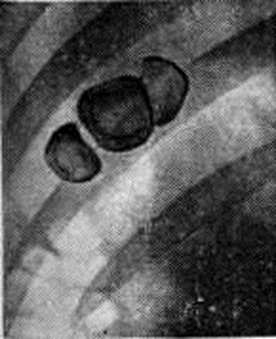

Рис. 2.

Обзорная рентгенограмма правого подреберья при калькулёзном холецистите: видны тени рентгеноконтрастных конкрементов.

Окончательный диагноз хронический холецистита устанавливают после проведения рентгенологическое и инструментального обследований. Важным методом исследования при хронический холецистите является рентгенологический. Начинать обследование следует с обзорной рентгенографии (смотри полный свод знаний) области правого подреберья, при которой можно обнаружить тени рентгеноконтрастных камней (рисунок 2) или обызвествление стенок желчного пузыря (рисунок 3). После этого производят холецистографию (смотри полный свод знаний) или сочетанную холецистохолангиографию, позволяющие установить наличие в желчном пузыре камней, что проявляется дефектом наполнения (рисунок 4), а также выявить деформацию желчного пузыря (рисунок 5) и нарушение его функции при некалькулёзном холецистите. С помощью ультразвукового исследования определяют состояние стенки пузыря, наличие в нем конкрементов, а также сократительную способность желчного пузыря. Все большее распространение получают метод радиоизотопного исследования желчного пузыря (смотри цветной рисунок 12 и 13), а также компьютерная томография печени, желчного пузыря (рисунок 6) и поджелудочной железы, которые применяются прежде всего у больных с желтухой и у лиц, которым противопоказано (например, в связи с аллергией) обычное рентгенологическое исследование. У больных с желтухой и (или) при непереносимости контрастного вещества (при его внутривенном введении) для уточнения диагноза можно произвести ретроградную холангиографию (смотри полный свод знаний) во время фибродуоденоскопии. Это даёт возможность получить прямое контрастирование желчного пузыря, позволяющее при некалькулёзном холецистите выявить его деформацию (рисунок 7) и нарушение оттока желчи, при калькулёзном холецистите — конкременты в просвете желчного пузыря, а иногда в общем желчном протоке.